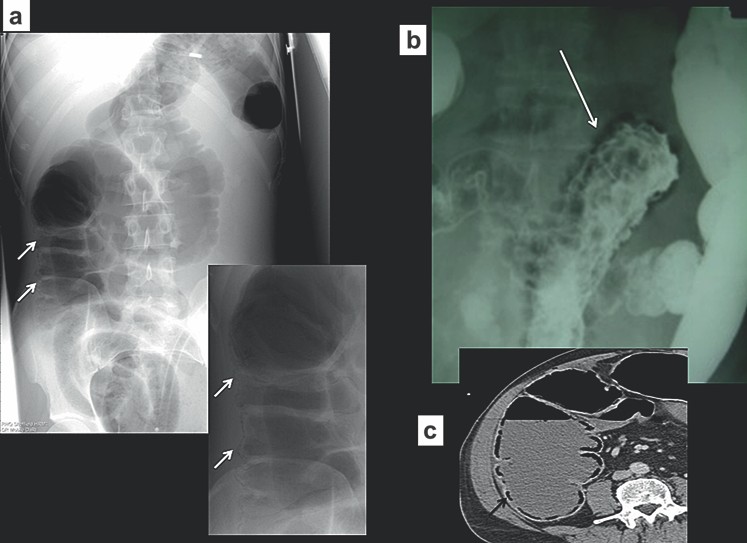

Xoắn manh tràng ít xảy ra so với xoắn đại tràng sigma, chỉ chiếm dưới 5% các trường hợp tắc đại tràng. Xoắn thường ở những người trung niên, điển hình là những người không có tiền sử phẫu thuật ổ bụng. Xoắn ở đại tràng lên, vị trí điển hình là ngay trên van hồi-manh tràng. Phim X quang bụng thường cho phép chẩn đoán và cho thấy quai ruột giãn to kéo từ hố chậu phải đến góc phần tư trên trái ổ bụng. Ruột non thường giãn và đại tràng ở đầu xa bị xẹp. Chụp cắt lớp vi tính hiếm khi được yêu cầu để khẳng định chẩn đoán, nhưng mục đích để phát hiện mạc treo bị xoắn và đoạn ruột bị thiếu máu hoặc thủng (Hình 5).

Hình 5. Xoắn manh tràng (a) Phim X quang bụng đứng thấy một quai ruột giãn nhô vào góc trên trái ổ bụng. Lưu y không có khí trong các đoạn đại tràng, các quai ruột non giãn to (b, c) Chụp CT xác định xoắn manh tràng, cũng thấy hình “mỏ chim” của mạc treo manh tràng xoắn.

Tắc ruột do sỏi mật (gallstone ileus) gây khí trong đường mật. Hiện tượng này xảy ra khi một sỏi lớn bào mòn thành túi mật và rơi vào ruột non. Sỏi thường nằm ở đoạn cuối hồi tràng, gây tắc ruột non. Tam chứng X quang cổ điển trên phim X quang bụng thường quy là ruột non bị giãn, khí trong đường mật (pneumobilia) và sỏi mật vôi hóa.

Những đặc điểm trên chỉ thấy trong 50% các trường hợp (Hình 8). Tắc ruột do sỏi mật là một nguyên nhân quan trọng của tắc ruột non, nên cân nhắc tới nguyên nhân này đặc biệt ở những bệnh nhân nữ nhiều tuổi.

Hình 8. Tắc ruột do sỏi mật (a) Phim X quang bụng thấy khí ở trong hệ thống đường mật (b) Phim X quang cho thấy tắc tại vị trísỏi (c, d) Chụp CT xác định khí trong đường mật và sỏi mật gây tắc ở đoạn xa hỗng tràng.